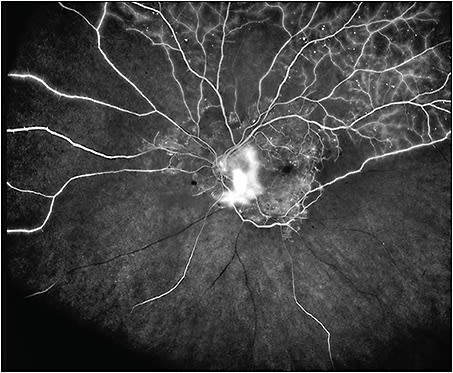

The advent of modern wide and ultrawidefield imaging devices has expanded our view of the peripheral retina and thus our perspective on DR. The Optos (Daytona; Optos), Clarus 500 (Carl Zeiss Meditec), and Clarus 700 (Carl Zeiss Meditec) are currently available widefield imaging platforms that both enable widefield imaging either in single capture or image montage.5 Optos is a scanning laser ophthalmoscope that produces retinal images of up to 200° in nonmydriatic eyes, representing more than three times the retinal surface of traditional ETDRS 7-field photos. This allows for identification of peripheral DR lesions that cannot be seen on conventional fundus photos. The recently released Clarus 500 and Clarus 700 capture “true-color” images that may potentially enable more accurate identification of DR lesions, although this has yet to be demonstrated in clinical trials.

Single-center studies have shown moderate to substantial agreement between the ETDRS 7-field system and UWF imaging in assessing DR severity.7-9 In a recent cross-sectional study comparing the 2 imaging systems using 37 DRCR.net sites, Aiello et al found that 59% of eyes had exact agreement and 97% of eyes were within 1 step of agreement.10 These findings may justify UWF imaging for assessing the severity of DR endpoints in future clinical trials. In other studies, DR was classified at a higher retinopathy level in the UWF view compared to ETDRS standard fields.11,12 Detection of retinal nonperfusion and neovascularization was also higher in UWF images, and the study authors suggested that improved retinal visualization may lead to more precise grading of disease compared to non-UWF images.

In clinical practice, the integration of UWF imaging enhances the ability to visualize the retinal periphery and may improve rates of DR detection. Recent studies suggest that the presence of predominantly peripheral lesions (PPL) on UWF imaging is highly associated with increased risk of DR worsening and the onset of proliferative DR. Predominantly peripheral lesions have been defined as microaneurysms, hemorrhages, venous beading, intraretinal microvascular abnormalities, and new vessels elsewhere in eyes with DR with more than 50% of the graded lesion located outside the 7 standard ETDRS fields.12,13 Using UWF imaging, Silva et al showed that eyes with PPLs have a 3.2-fold increased risk of 2-step or more of DR progression and a 4.7-fold increased risk for progression to proliferative disease, independent of baseline DR severity and HbA1C levels.14 These findings demonstrate that evaluation of the peripheral retina using UWF imaging provides important information for assessing the risk of DR progression that cannot be assessed by ETDRS 7-field imaging. The use of UWF imaging also may be important in clinical trial settings requiring precise assessment of prospective DR progression rates, in clinical care for accurate patient counseling, and in teleophthalmology programs to improve risk assessment and triage in eyes that otherwise would not have the peripheral retina evaluated.